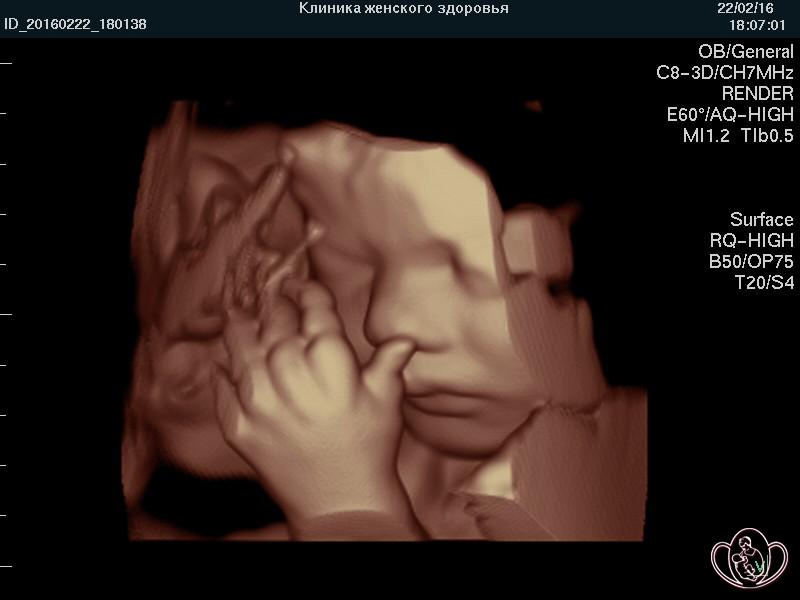

Плод на 38 неделе беременности . Вес ребенка на 38 неделе беременности, как и его рост, продолжает увеличиваться день ото дня . Масса тела достигает 3 кг, а рост - 50 см .

Как ведет себя плод на 38 неделе беременности . У малыша на сроке 38 недели хорошо развились все органы, вся система подготовлена и функционирует для того, чтобы появиться на свет ( 38 неделя беременности показана на фото . . .

Плод на 38 неделе беременности: шевеления, вес и размеры Хоть роды могут произойти в любой из дней этой недели, пока они не наступили - беременность продолжается .